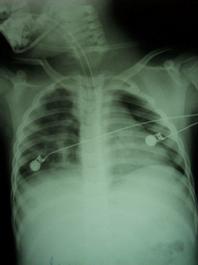

TRAUMATISME TORACICE

Emfizem subcutanat

Emfizem subcutanat Emfizem subcutanat

Aspect radiologic Imagine CT